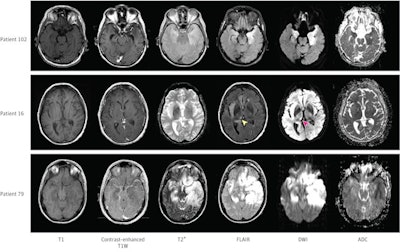

These changes often manifest as thalamic diffusion signal variations, and awareness of them could help clinicians manage HSE patients better, wrote a team led by Dr. Benjamine Sarton of the University Hospital of Purpan in Toulouse, France.

The research included 138 patients diagnosed with encephalitis who tested positive for herpes simplex virus in their cerebrospinal fluid between 2007 to 2019 at 34 ICUs in France. The patients underwent a standard brain MRI exam within 30 days of admission; for the study, these exam findings were analyzed by radiologist readers blinded to patient outcomes. Poor outcomes at 90 days after ICU admission were scored on a scale of three to six (moderate-to-severe disability or death).

"We observed that the total amount of neuroinflammatory lesions, which were mainly identified by FLAIR [fluid-attenuated inversion recovery] acquisitions, was significantly associated with patients' functional outcomes," the group wrote.

"In this cohort study of patients with HSE, the presence of extensive MRI lesions, on both FLAIR and [diffusion-weighted imaging (DWI)] sequences, was independently associated with poor functional outcome at 90 days," the group wrote. "Thalamic DWI hyperintensities were frequently observed and were associated with poor prognosis, mainly in older patients. Future studies should focus on prospectively testing the prognostic value of these neuroimaging markers."